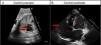

Patient aged 15 months with right atrial appendage enlargement diagnosed prenatally at 20 weeks’ gestational age, with an area of 1.6cm2 detected in the four-chamber view at 35 weeks’ gestation. She was admitted to the hospital for twenty-four hours after an uncomplicated delivery at 40.1weeks’ gestation for observation and cardiac monitoring, and had no arrhythmia or other complications. The atrial appendage size has remained constant during the followup, with an area of 3.5cm2 observed in the four-chamber view. There has been no evidence of intra-auricular thrombi (Fig. 2). In this patient, given the absence of symptoms and complications, we adopted a watchful waiting approach and did not initiate treatment.

Case 2. Right atrial appendage enlargement. (A) Foetal ultrasound at 22 weeks’ gestation, arrow points at right atrial enlargement. (B) Postnatal follow-up ultrasound at 1 year of life showing enlargement of the right atrial appendage 6mm in diameter (arrow). AD, right atrium; AI, left atrium; VD, right ventricle; VI, left ventricle.